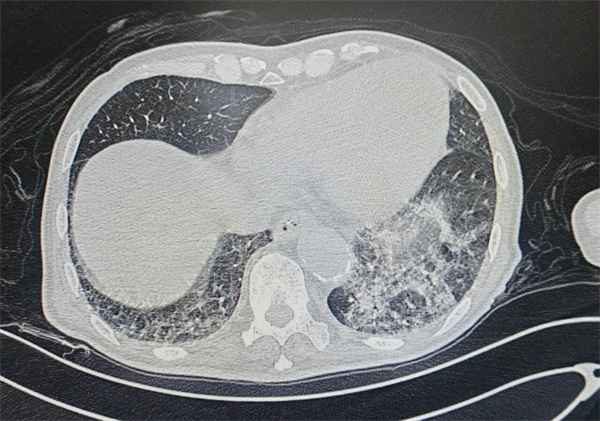

为明确病因并制定针对性治疗方案,呼吸内科刘前桂主任医师为患者进行了床旁气管镜检查。检查中发现,患者气道内积聚大量脓痰,尤其左下肺区域的痰液粘稠度极高,难以直接吸出。刘前桂主任医师团队随即采用生理盐水反复冲洗气道,随着视野逐渐清晰,一个异物的轮廓在左下叶基底段支气管内显现——这正是导致高先生反复感染的“罪魁祸首”。

11月21日上午,手术在充分的镇静与镇痛保障下正式开始。吴海玲副主任医师操作气管镜,凭借丰富的临床经验,先逐步吸除气道内残留痰液,彻底暴露异物位置。术中清晰可见,异物为一颗形态细长的脱落牙齿,深深嵌顿在直径仅约2mm的左下叶后基底段支气管远端,周围还包裹着大量分泌物,手术难度远超常规气道异物取出术。